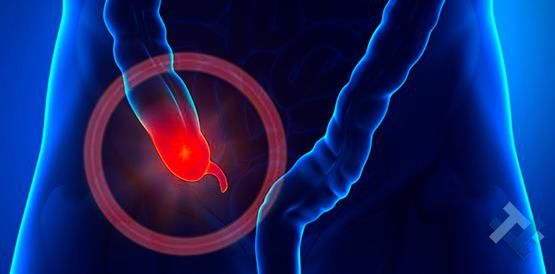

Ο Γενικός Χειρουργός Λιάγκος Γεώργιος MD PhD εκτελεί τις επεμβάσεις Λαπαροσκοπικά, Ενδοσκοπικά, Ανοιχτά Ελάχιστα Επεμβατικά και με Laser. Η θεραπεία εξατομικεύεται σε κάθε ασθενή ανάλογα με τις ανάγκες του. Αναλαμβάνει περιπτώσεις όπως κήλες και κοιλιοκήλες (αντιμετώπιση βουβωνοκήλης, αντιμετώπιση ομφαλοκήλης, θεραπεία επιγαστρικής κήλης, κήλη των αθλητών (Σύνδρομο κοιλιακών προσαγωγών), αντιμετώπιση μετεγχειρητικής κήλης, θεραπεία Μηροκήλης), πέτρες στη χοληδόχο κύστη, λαπαροσκοπική χολοκυστεκτομή, αντιμετώπιση Κύστη Κόκκυγος με λέιζερ (laser), παθήσεις πρωκτού, χειρουργική laser σύγχρονων κυκλικών ινών (αιμορροΐδες αντιμετώπιση, θεραπεία αιμορροϊδων με laser (LHP), αφαίρεση αιμορροΐδων με υπερήχους (HALL-RAR), χωρίς Χειρουργείο με ελαστικούς δακτυλίους (Τεχνική BARON-RBL), θεραπεία ραγάδας πρωκτού (Ραγάδα δακτυλίου), θεραπεία περιεδρικού συριγγίου, θεραπεία περιεδρικού αποστήματος, κονδυλώματα πρωκτού Θεραπεία, δερματικό ράκος (Skin tag) εκτομή, αντιμετώπιση Kνησμού, καρκίνος πρωκτού θεραπεία), παθήσεις Δέρματος, χειρουργική με laser CO2, αφαίρεση μορφωμάτων δέρματος - βιοψίες, αφαίρεση ελιάς (Σπίλου), σμηγματογόνος κύστης θεραπεία, αφαίρεση λιπώματος, είσφρυση όνυχος χειρουργείο, καρκίνος δέρματος θεραπεία, οξεία σκωληκοειδίτιδα, παθήσεις Λεπτού και Παχέος Εντέρου, ειλεός λεπτού εντέρου, εκκολπωμάτωση (Εκκολπωματίτιδα) σιγμοειδούς, καρκίνος παχέος εντέου, κολοστομίες, port χημειοθεραπείας κ.α.

Ο Γενικός Χειρουργός Λιάγκος Γεώργιος MD PhD εκτελεί τις επεμβάσεις Λαπαροσκοπικά, Ενδοσκοπικά, Ανοιχτά Ελάχιστα Επεμβατικά και με Laser. Η θεραπεία εξατομικεύεται σε κάθε ασθενή ανάλογα με τις ανάγκες του. Αναλαμβάνει περιπτώσεις όπως κήλες και κοιλιοκήλες (αντιμετώπιση βουβωνοκήλης, αντιμετώπιση ομφαλοκήλης, θεραπεία επιγαστρικής κήλης, κήλη των αθλητών (Σύνδρομο κοιλιακών προσαγωγών), αντιμετώπιση μετεγχειρητικής κήλης, θεραπεία Μηροκήλης), πέτρες στη χοληδόχο κύστη, λαπαροσκοπική χολοκυστεκτομή, αντιμετώπιση Κύστη Κόκκυγος με λέιζερ (laser), παθήσεις πρωκτού, χειρουργική laser σύγχρονων κυκλικών ινών (αιμορροΐδες αντιμετώπιση, θεραπεία αιμορροϊδων με laser (LHP), αφαίρεση αιμορροΐδων με υπερήχους (HALL-RAR), χωρίς Χειρουργείο με ελαστικούς δακτυλίους (Τεχνική BARON-RBL), θεραπεία ραγάδας πρωκτού (Ραγάδα δακτυλίου), θεραπεία περιεδρικού συριγγίου, θεραπεία περιεδρικού αποστήματος, κονδυλώματα πρωκτού Θεραπεία, δερματικό ράκος (Skin tag) εκτομή, αντιμετώπιση Kνησμού, καρκίνος πρωκτού θεραπεία), παθήσεις Δέρματος, χειρουργική με laser CO2, αφαίρεση μορφωμάτων δέρματος - βιοψίες, αφαίρεση ελιάς (Σπίλου), σμηγματογόνος κύστης θεραπεία, αφαίρεση λιπώματος, είσφρυση όνυχος χειρουργείο, καρκίνος δέρματος θεραπεία, οξεία σκωληκοειδίτιδα, παθήσεις Λεπτού και Παχέος Εντέρου, ειλεός λεπτού εντέρου, εκκολπωμάτωση (Εκκολπωματίτιδα) σιγμοειδούς, καρκίνος παχέος εντέου, κολοστομίες, port χημειοθεραπείας κ.α.